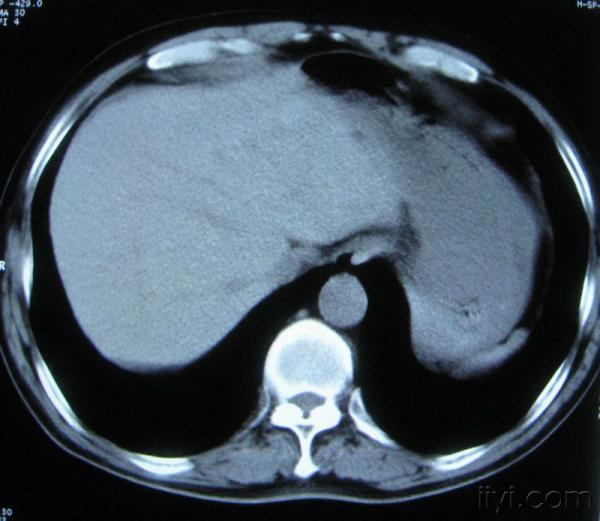

男。60岁,胸片示支气管炎治疗后复查CT。

你指那个肯定是淋巴结,中央系坏死,这很常见,特别在双侧腹股沟会经常看到。这个双侧腋窝及纵隔见多发小淋巴结征。

根据位置考虑应该是淋巴结,密度不均,是因为肿大的淋巴结中心液化坏死